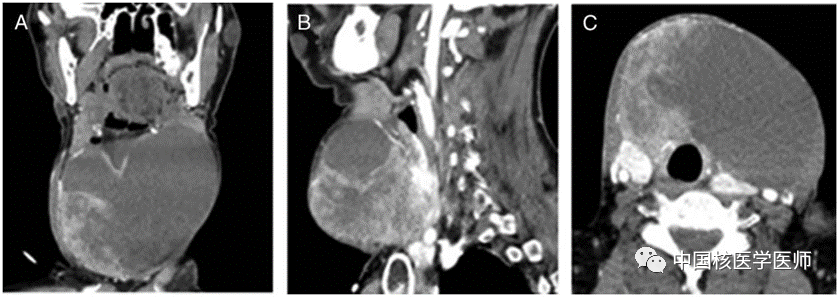

圖2. 圖A–C, 18F-FDG PET/CT顯像結(jié)果顯示,異質(zhì)性軟組織腫塊呈高代謝活性。在所有年齡段普通人群中,原發(fā)性甲狀舌管癌的發(fā)病率低于1%。在這類癌癥中,88%為甲狀腺乳頭狀癌,6%為鱗狀細(xì)胞癌,其余為Huthle細(xì)胞癌、濾泡性甲狀腺癌和間變性甲狀腺癌。甲狀舌管癌不容易診斷,直到它變得足夠大時(shí),可以在CT成像、核磁共振成像或超聲檢查中發(fā)現(xiàn)。